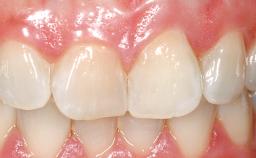

A 33-year-old female patient presented with an upper left central incisor that required extraction after a failed endodontic therapy. The tooth had been traumatized when the patient was a teenager and had undergone several endodontic treatments, including two apicectomy procedures. The patient was in good health and did not smoke. Clinical examination showed that the patient had a high lip line. In full smile, the gingival margins of the upper teeth were visible to the first molars. The gingival margins of central incisors 11 and 21 were only just showing. Examination of tooth 21 confirmed that the tooth was mobile and had hypererupted by 1 mm.

Soft Tissue Contour and Volume | Slightly compromised |